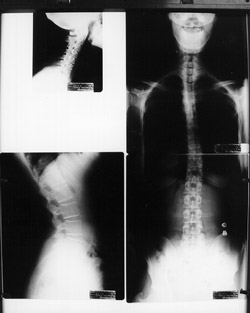

Spinal X-rays may be taken depending on your age, and situation. There are many reasons why we would not take x-rays on certain patients including pregnancy, most children, recent usable spinal x-rays and some other various situations. Aside from these situations, x-rays are a common part of the examination process when looking for vertebral subluxations. X-rays give us important information including the position of the spinal bones, and the quality of the spine and safety of adjusting it. With this important information we can make a more accurate determination of the type of adjustments your spine needs as well as the ongoing frequency of your care. Your x-rays will be explained to you and covered in detail.